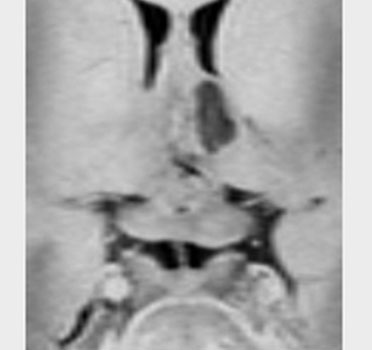

非常に典型的な下垂体後葉germinomaの画像です。萎縮して残った前葉線組織が前方にありガドリニウム増強されます。薄く増強されているトルコ鞍背部がgerminomaです。経蝶形骨洞手術で下垂体底面をもちあげて生検を行いました。

CBDCA/VP-16 3コースの後で,全脳室照射25.2Gy/14frを加えて治癒しています。成長ホルモンで身長も伸びて,11年が経過し,社会人として普通に暮らせています。